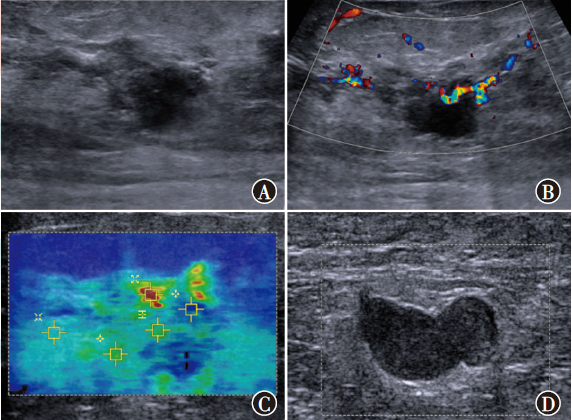

目的 探讨常规超声联合剪切波弹性成像(SWE)鉴别诊断非肿块型导管原位癌(DCIS)和浸润性乳腺癌(IBC)的价值。方法 选取2019年3月至2022年4月在南京大学医学院附属鼓楼医院收治的102例非肿块型乳腺癌患者作为研究对象,其中DCIS 32例、IBC 70例。比较非肿块型DCIS、IBC患者常规超声参数回声、微钙化、方位、后方回声、血流、腋窝淋巴结、乳腺影像报告与数据系统(BI-RADS)评分及SWE相关参数剪切波速度最大值(SWVmax)、剪切波速度最小值(SWVmin)、剪切波速度平均值(SWVmean)和剪切波速度中位数(SWVmedian),采用二元logistic回归分析鉴别诊断非肿块型DCIS和IBC的独立影响因素。根据多因素分析结果构建列线图预测模型,采用受试者操作特征(ROC)曲线评估预测模型的预测效能,采用校准曲线及决策曲线分析(DCA)评估模型的准确性和实用性。结果 非肿块型DCIS、IBC患者间血流(χ2=8.47,P=0.004)、腋窝淋巴结(χ2=9.11,P=0.003)、SWVmaxZ=-3.32,P<0.001)、SWVmeant=3.00,P=0.003)、SWVmedianZ=-2.69,P=0.007)差异均有统计学意义。多因素分析显示,血流(OR=3.56,95%CI为1.28~9.89,P=0.015)、腋窝淋巴结(OR=3.04,95%CI为1.10~8.42,P=0.032)和SWVmaxOR=1.40,95%CI为1.13~1.73,P=0.002)均为鉴别诊断非肿块型DCIS和IBC的独立影响因素。基于血流、腋窝淋巴结、SWVmax构建列线图预测模型。ROC曲线分析显示,血流、腋窝淋巴结、SWVmax、预测模型鉴别诊断非肿块型DCIS和IBC的曲线下面积分别为0.64(95%CI为0.52~0.76)、0.66(95%CI为0.55~0.77)、0.71(95%CI为0.60~0.81)、0.79(95%CI为0.70~0.88),预测模型的鉴别诊断价值高于血流(Z=2.92,P=0.004)、腋窝淋巴结(Z=2.94,P=0.003)、SWVmaxZ=1.88,P=0.060)单独诊断。预测模型鉴别诊断非肿块型DCIS和IBC的C-index为0.77,校准曲线显示模型的预测概率接近实际概率。DCA表明,该模型能提供较高的临床净获益,具有一定的临床实用性。结论 常规超声参数中的血流、腋窝淋巴结和SWE相关参数的SWVmax均为鉴别诊断非肿块型DCIS和IBC的独立影响因素,以此构建的列线图预测模型对非肿块型DCIS和IBC具有较高的鉴别诊断价值。

Objective To investigate the value of conventional ultrasound combined with shear wave elastography (SWE) in the differential diagnosis of non-mass ductal carcinoma in situ (DCIS) and invasive breast cancer (IBC). Methods A total of 102 patients with non-mass breast cancer admitted to Nanjing Drum Tower Hospital, Affiliated Hospital of Nanjing University Medical School from March 2019 to April 2022 were selected as the study objects, including 32 cases of DCIS and 70 cases of IBC. Conventional ultrasound parameters echo, microcalcification, location, posterior echo, blood flow, axillary lymph node, breast imaging reporting and data system (BI-RADS) score and SWE-related parameters maximum shear wave velocity (SWVmax), minimum shear wave velocity (SWVmin), mean shear wave velocity (SWVmean) and median shear wave velocity (SWVmedian) were compared between patients with non-mass DCIS and IBC. Binary logistic regression was used to analyze the independent factors for the differential diagnosis of non-mass DCIS and IBC. Based on the results of multivariate analysis, a nomogram prediction model was constructed and the predictive efficacy of the prediction model was evaluated by receiver operator characteristic (ROC) curve. Calibration curve and decision curve analysis (DCA) were used to evaluate the accuracy and practicability of the model. Results There were statistically significant differences in blood flow (χ2=8.47, P=0.004), axillary lymph nodes (χ2=9.11, P=0.003), SWVmaxZ=-3.32, P<0.001), SWVmeant=3.00, P=0.003), SWVmedianZ=-2.69, P=0.007) between patients with non-mass DCIS and IBC. Multivariate analysis showed that, blood flow (OR=3.56, 95%CI: 1.28-9.89, P=0.015), axillary lymph nodes (OR=3.04, 95%CI: 1.10-8.42, P=0.032) and SWVmaxOR=1.40, 95%CI: 1.13-1.73, P=0.002) were independent factors for distinguishing non-mass DCIS from IBC. A nomogram prediction model was constructed based on blood flow, axillary lymph nodes and SWVmax. ROC curve analysis showed that, the area under the curve of blood flow, axillary lymph nodes, SWVmax, and prediction model for differential diagnosis of non-mass DCIS and IBC were 0.64 (95%CI: 0.52-0.76), 0.66 (95%CI: 0.55-0.77), 0.71 (95%CI: 0.60-0.81), and 0.79 (95%CI: 0.70-0.88), respectively, and the differential diagnostic value of prediction model was higher than that of blood flow (Z=2.92, P=0.004), axillary lymph nodes (Z=2.94, P=0.003), and SWVmaxZ=1.88, P=0.060) alone. The C-index of the prediction model for the differential diagnosis of non-mass DCIS and IBC was 0.77, and the calibration curve showed that the prediction probability of the prediction model was close to the actual probability. DCA showed that this prediction model could provide higher clinical net benefit and had certain clinical practicability. Conclusion Blood flow and axillary lymph nodes in conventional ultrasound parameters and SWVmax of SWE-related parameters are independent factors in the differential diagnosis of non-mass DCIS and IBC. The nomogram prediction model constructed by this method has a high value in the differential diagnosis of non-mass DCIS and IBC.